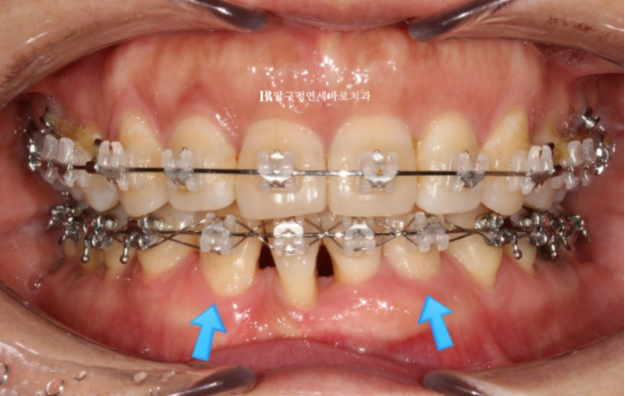

어느정도 배열이 잡힌 후에 나머지 앞니 1개를 더 뺍니다.

23.10

발치한 빈 공간에는 환자분의 품위 유지를 위해 가짜 이를 달았고

이 후 몇달간 치료 끝에

파란 화살표는 송곳니이고 앞니 자리로 잘 이동했습니다.

교합도 좋습니다.